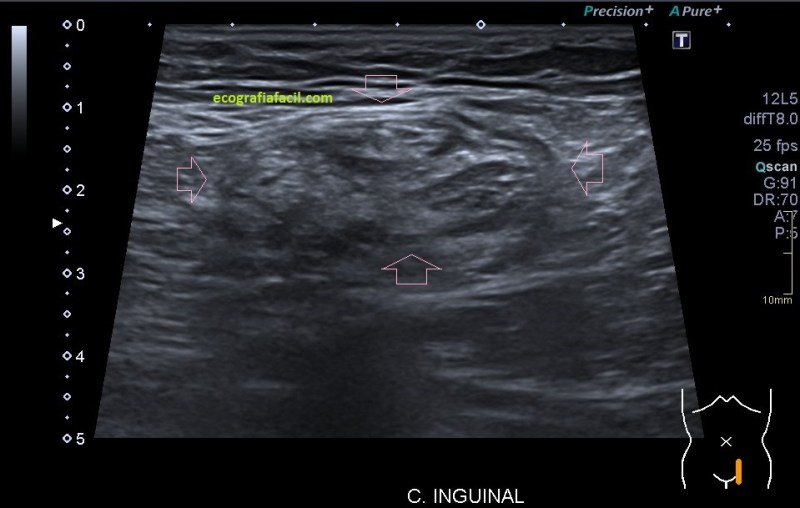

En segundo término, la heterogenicidad global de la imagen, clave para el diagnóstico, la semiología tan llamativa de la ecoarquitectura.

La anatomía ecográfica no deja lugar a dudas de la localización llegando muy cerca del testículo, ocupando el canal inguinal.

La lesión era bastante grande , ocupaba como ves en la imagen una parte importe del canal inguinal también en la imagen 7.

Se completa estudio con Ct ante las características de la lesión y la imagen que tenemos, muy llamativa, refrenda la presencia de una lesión en el canal inguinal que posee una gran calcificación.  En el CT se objetiva, imagen 7, una afectación ligeramente mayor a la estimada en el estudio ecográfico. La sospecha para la radióloga fue de lesión primaria de cordón inguinal compatible con Liposarcoma, a tenor de todos lo hallazgos en las dos pruebas, basándose principalmente en la heterogenicidad de la imagen, la calcificación y el comportamiento no compatible con hernia inguinal ni con la semiología típica del lipoma.

Es muy importante que tengamos en cuenta algunas características semiológicas que no debemos dejar pasar y de las que he hablado a lo largo de muchísimos post y que deben ser líneas rojas. Es decir, hallazgos que siempre deben hacernos sospechar de que las características de la lesión no son compatibles con benignidad en el contexto del estudio de los lipomas y son, repito una vez más:

Heterogenicidad de la imagen, vascularización de la lesión y comportamiento anómalo como puede ser su dureza y su crecimiento rápido.